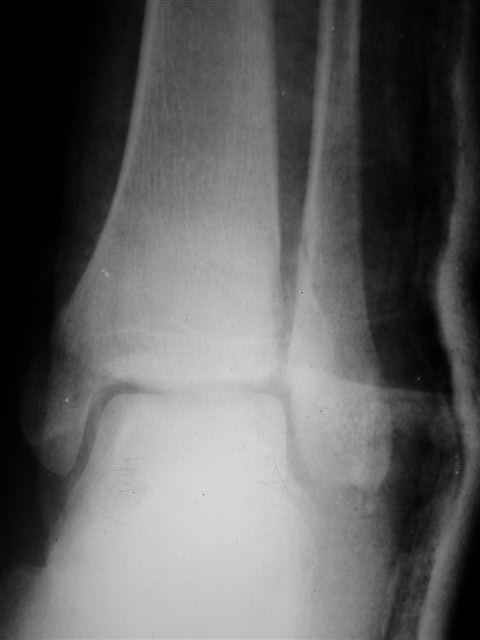

Re: открытый перелом мыщелков бедра, латерального

Я предупреждал, что ничего сверхъестественного. Каюсь, что одна из спиц прошла несколько дальше, чем нужно было, но главное - перелом стабилизирован и больной работает суставом в полном объёме, несмотря на представленную раннее травму коленного сустава.